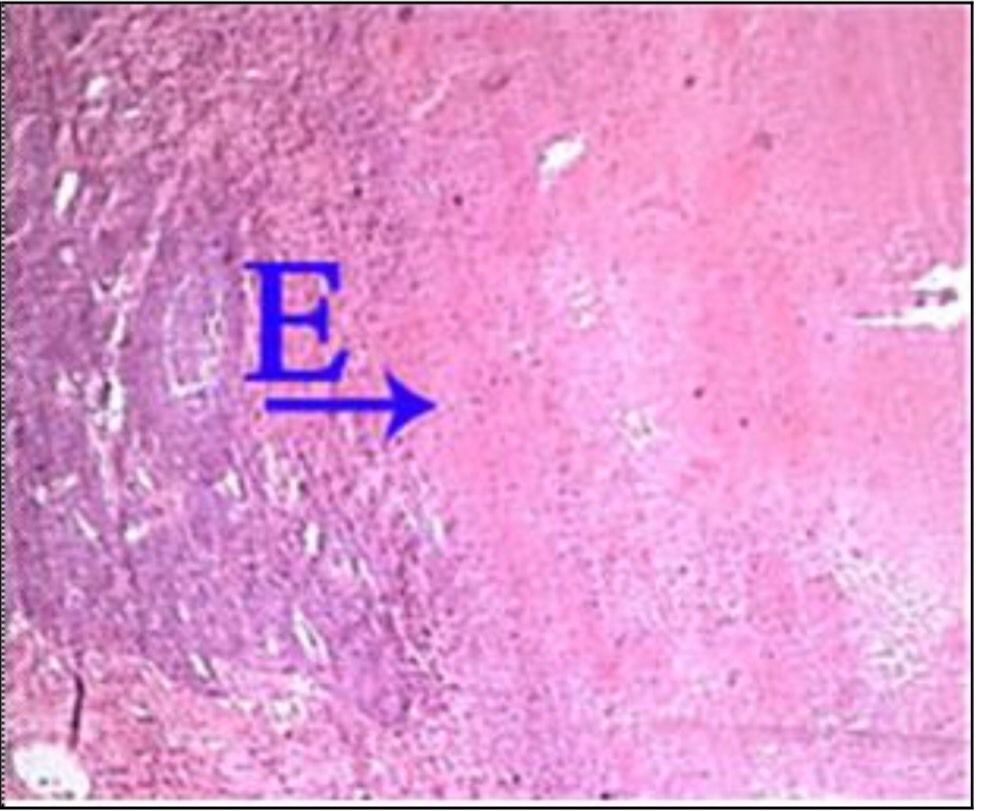

What is the correct answer at point E?

• - travées de sclérose annulaire

• - nodule cirrhotique, sans veine Centro lobulaire

• - néoformation canalicule biliaire

• - infiltration lymphocytaire

• - hépatocyte contenant de la bile